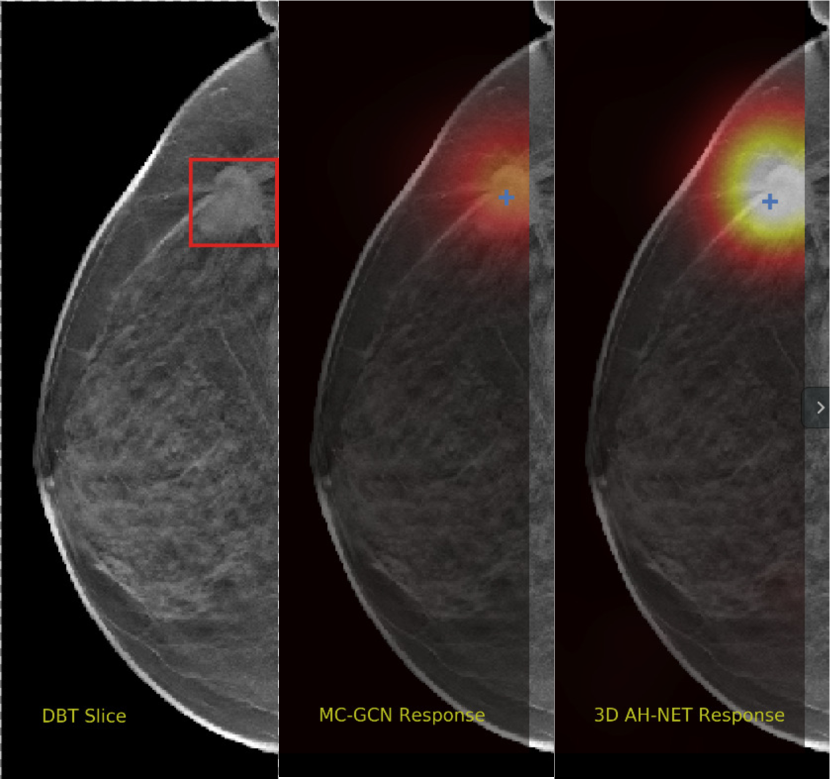

We selected some example slices from the DBT dataset to demonstrate the advantage of our proposed AH-Net for the Breast cancer screening. From Fig. 8 to Fig. 12, we show slices from five test DBT volumes that both the MC-GCN and the proposed 3D AH-Net could successfully detect the suspected breast lesion. The original DBT slice is shown on the left with the lesion annotated by our radiologist. Please note the original annotation is a 3D box. The figures in the middle and on the right are response maps from MC-GCN and 3D AH-Net overlaid on the original image, respectively. The detection locations obtained with non-maximal suppression are displayed with cross markers. As shown in the images, the proposed network can detect breast lesions varying in sizes and appearances. The confidence of the 3D AH-Net is usually higher than that of MC-GCN. From Fig. 13 to Fig. 17, we show five volumes that MC-GCN failed to detect the lesions since the lesions were not distinguishable from other breast tissues using the information within the slice. In contrast, 3D AH-Net was able to detect the lesions from such volumes using the 3D context between slices. As shown in Fig. 18 to Fig. 22, there are also volumes with lesions that both network failed to detect. Such lesions normally reside in the dense breast tissues. The boundary between these lesions and the normal breast tissues usually have low contrast. The networks sometimes also confuse them with other roundish structures in the breast such as lymph nodes or skin moles.

Refer to caption

Figure 16: Example DBT slice 9 with a lesion that can only be detected by 3D AH-Net. The lesion is highly blended within the dense breast tissues which makes it challenging for both the radiologists and the networks to detect with only a 2D view of the structure. The lesion can be detected by considering the consistency of the structure across a few neighbouring slices.

Figure 17: Example DBT slice 10 with a lesion that can only be detected by 3D AH-Net. The lesion is highly blended within the dense breast tissues which makes it challenging for both the radiologists and the networks to detect through a slice 2D slice. The lesion can be detected by considering the consistency of the structure across a few neighbouring slices.